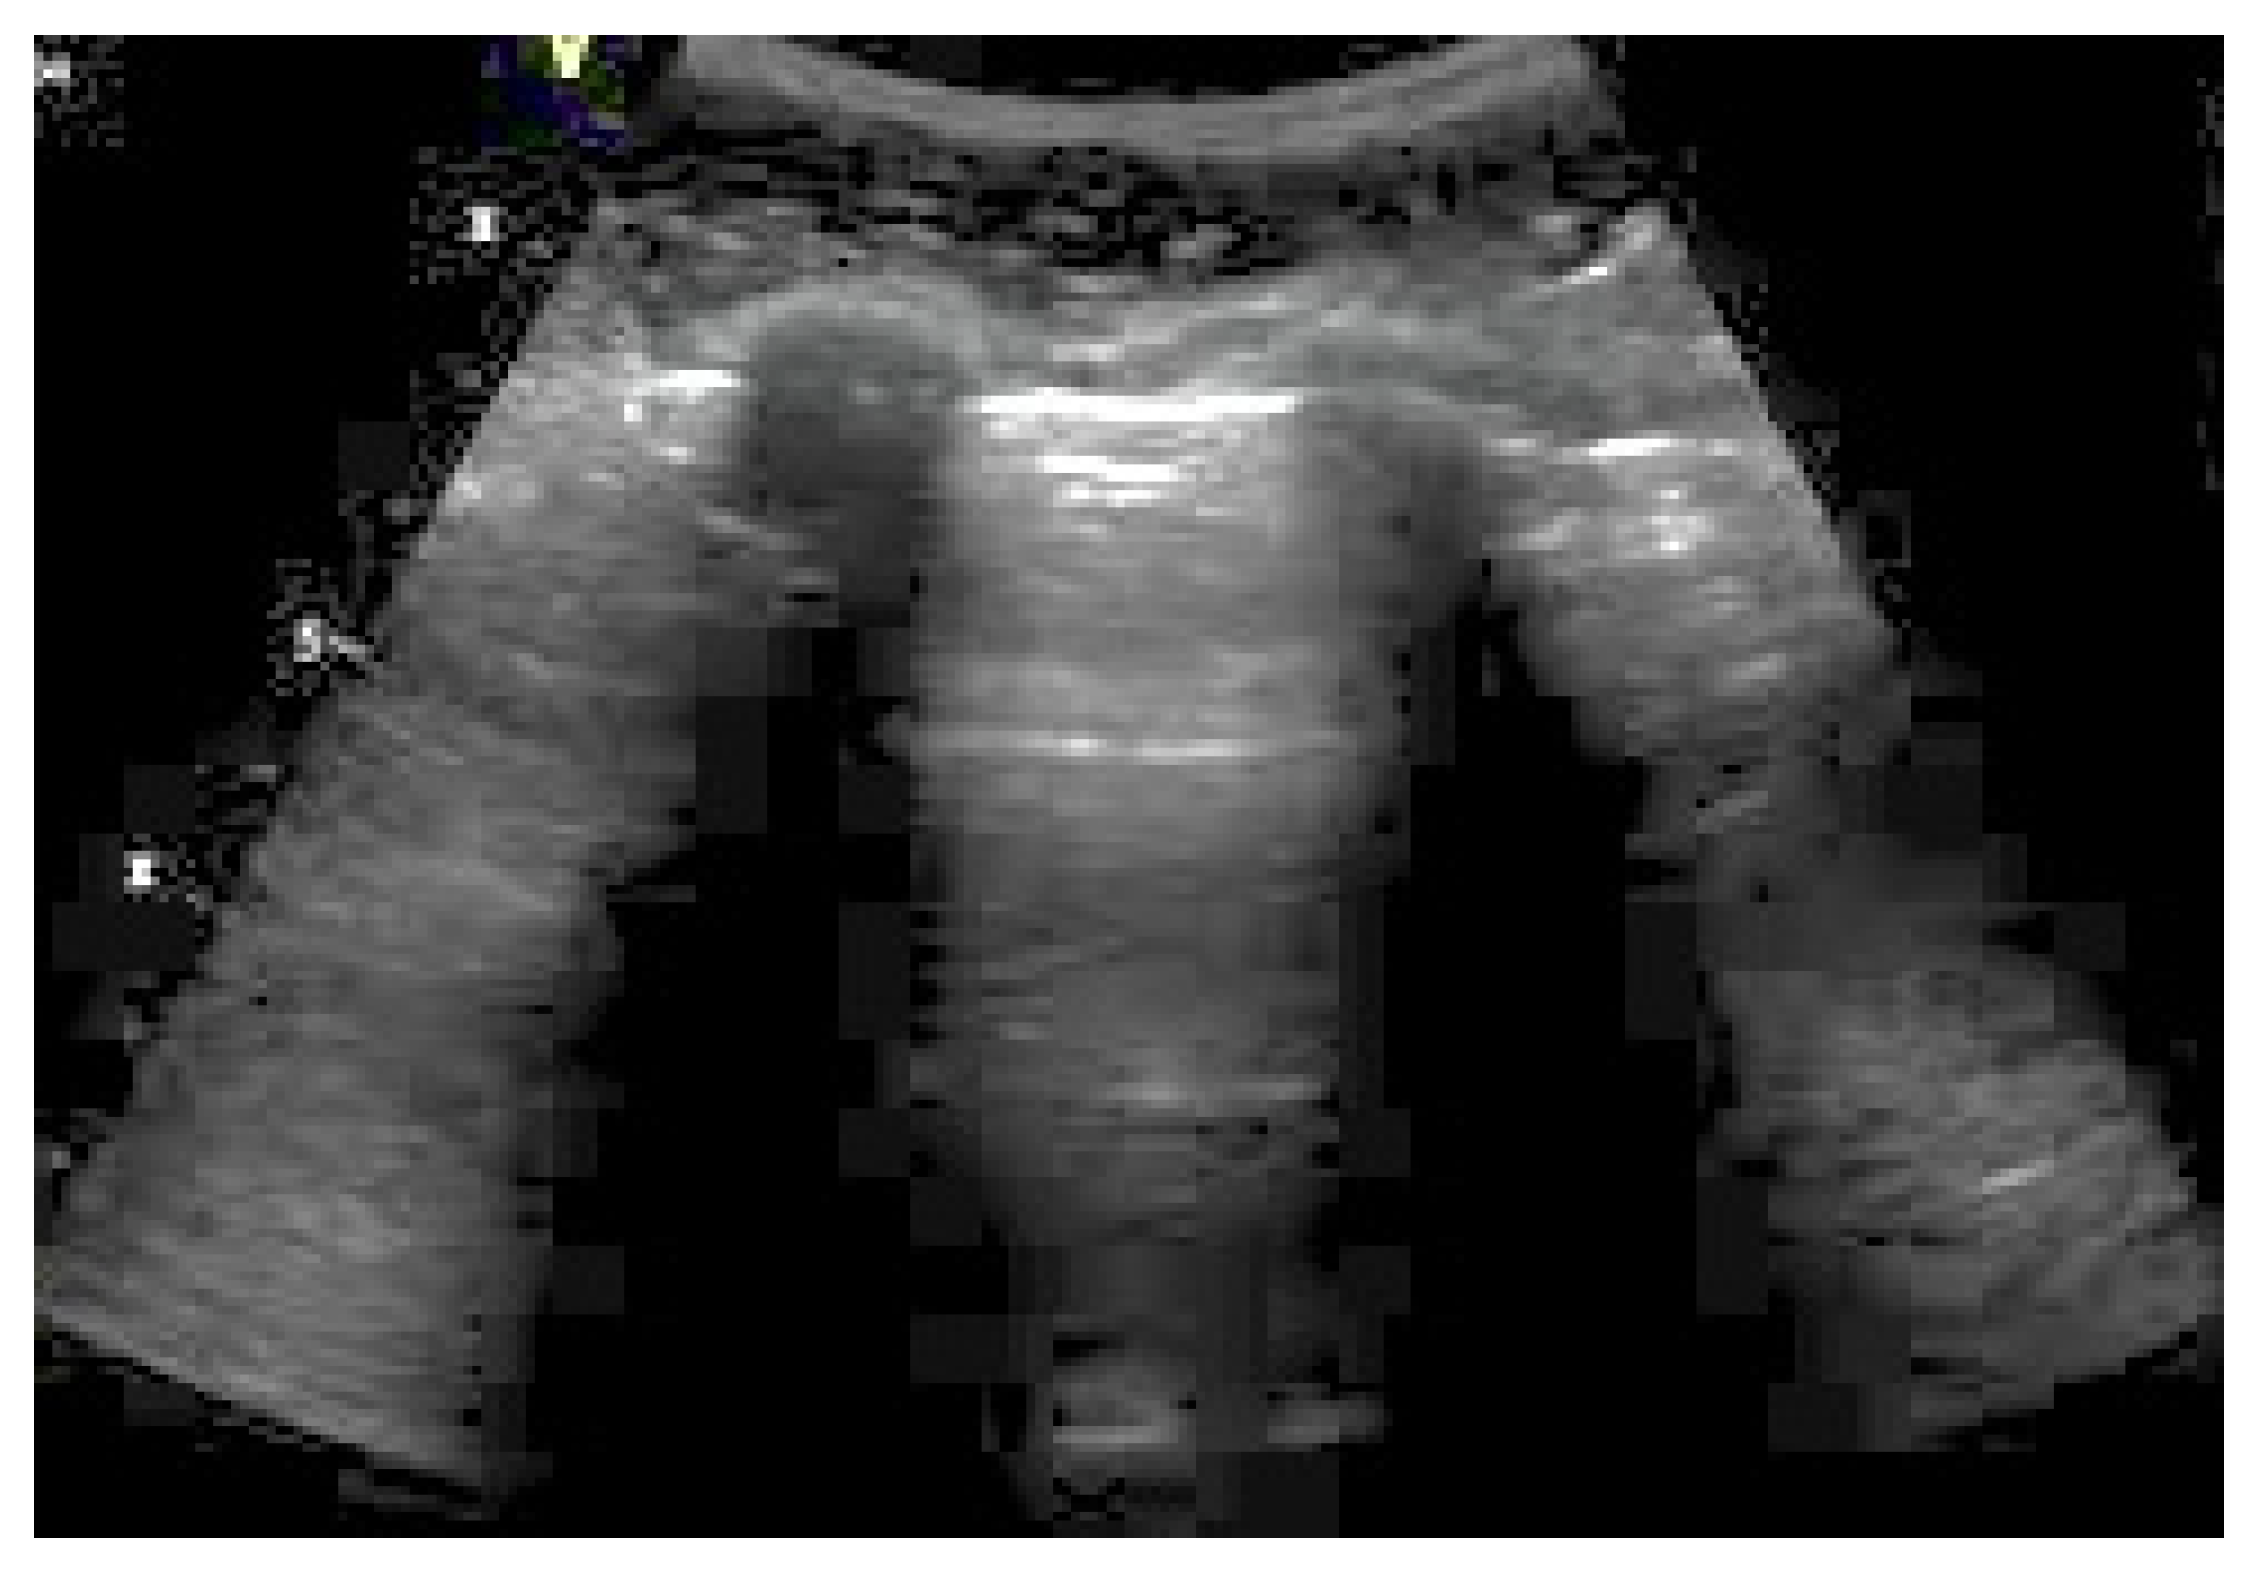

2.2.1. Pneumothorax

- (A)

- Abolition of lung sliding

- (B)

- A-lines

- (C)

- Lung point